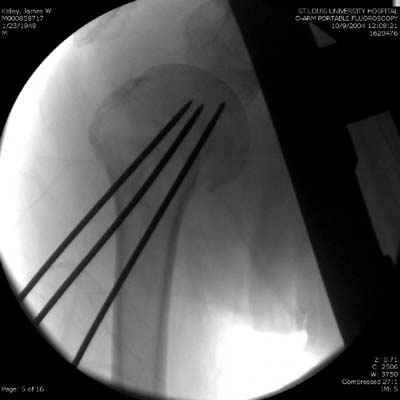

Здесь случай перелома-вывиха плеча, больному 56 лет, после "дважды" закрытой неудачной репозиции, опять же ургентно взяли в операционную, после полного общего обезболивания попытались сделать репозицию, и фиксацию провели спицами.

Больной находился в повязке, примерно напоминяющей косыночную, рекомендованы движения в локтевом суставе и маятниковые движения в плече, спицы удалены в три недели (были случаи миграции)

Больной амбулаторный, предупрежден на случай осложнения АВН головки.